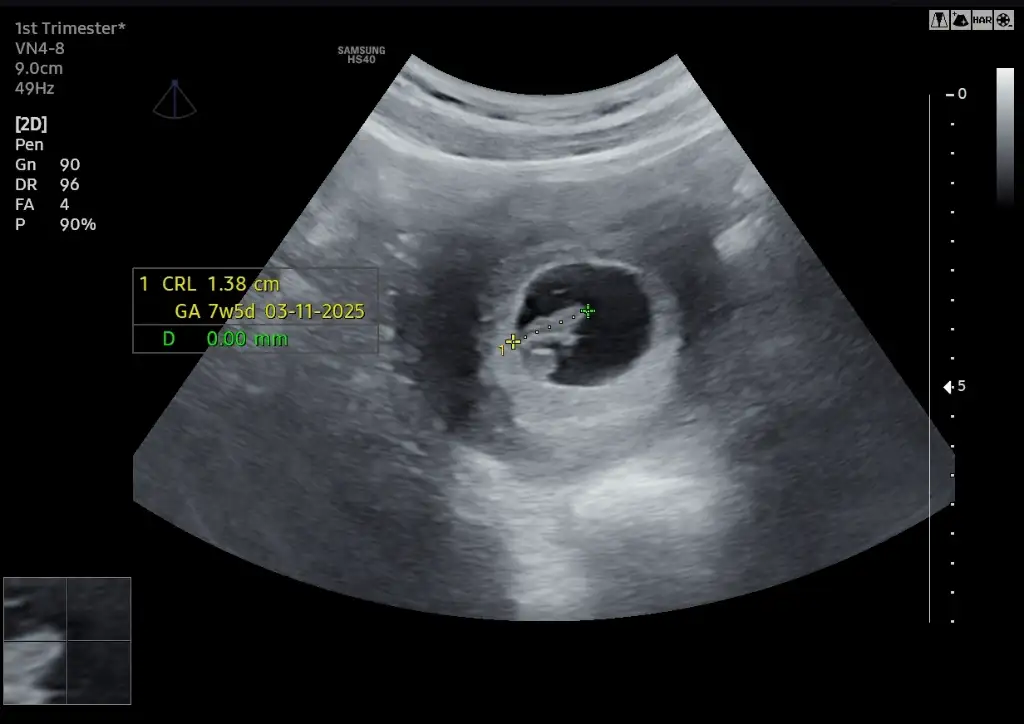

deneyimlediniz mii peki gebeliğinizdeEki Görüntüle 3565622 Ben bu teoriye dayanarak erkek diyorum

Tam net değil ama benimkinede yorum yapablrmsnz?Eki Görüntüle 3565622 Ben bu teoriye dayanarak erkek diyorum

KızTam net değil ama benimkinede yorum yapablrmsnz?